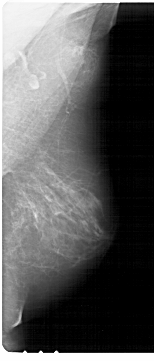

A_1370_1.LEFT_MLO

LEFT_MLO LINES 6871 PIXELS_PER_LINE 3541 BITS_PER_PIXEL 12 RESOLUTION 43.5 OVERLAY

FILE: A_1370_1.LEFT_MLO.OVERLAY

TOTAL_ABNORMALITIES 1

ABNORMALITY 1

LESION_TYPE MASS SHAPE IRREGULAR MARGINS ILL_DEFINED

ASSESSMENT 4

SUBTLETY 3

PATHOLOGY BENIGN

TOTAL_OUTLINES 1

BOUNDARY